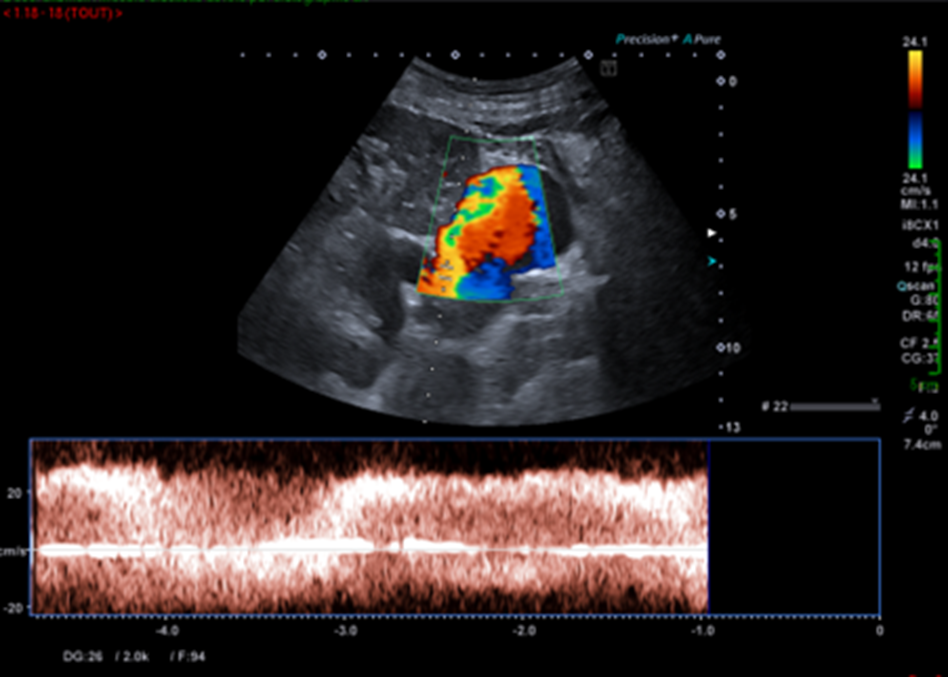

Celui qui aura balayé entièrement l’organe et son environnement, et qui aura complété son examen par le doppler couleur répondra différemment.

Ces nouvelles coupes (faisant apparaitre la rate, le doppler couleur et le doppler pulsé), montrent alors non pas un kyste rénal mais des volumineuses veines péri spléniques correspondant à des voies de dérivations spléno-rénales témoignant d’une hypertension portale probablement liée à la cirrhose sous-jacente.